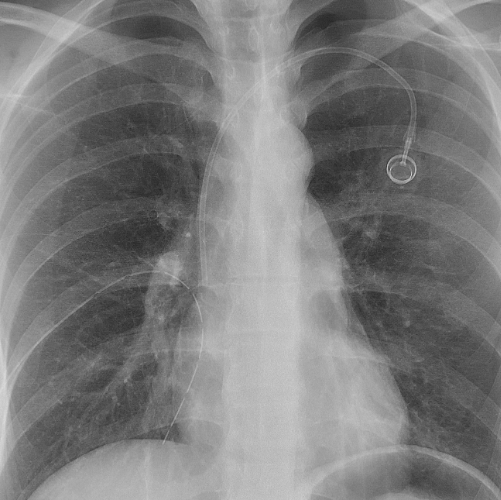

기흉이 심해지면 흉막강 내 공기가 계속 축적되어 폐와 심장을 압박하는 긴장성 기흉이 발생할 수 있는데, 이 상태는 생명을 위협하는 응급상황으로 혈압 저하, 청색증, 의식 저하 등이 나타나며 즉각적인 응급조치가 필요합니다. 진단 방법은 보통 흉부 X선 촬영으로, 허탈된 폐와 흉막강 내 공기를 확인하며, 더 정밀한 원인 분석과 확진을 위해 흉부 CT를 시행하기도 합니다. 청진 시에는 기흉이 있는 쪽 가슴에서 호흡음이 감소하거나 사라진 점도 진단에 도움이 됩니다.